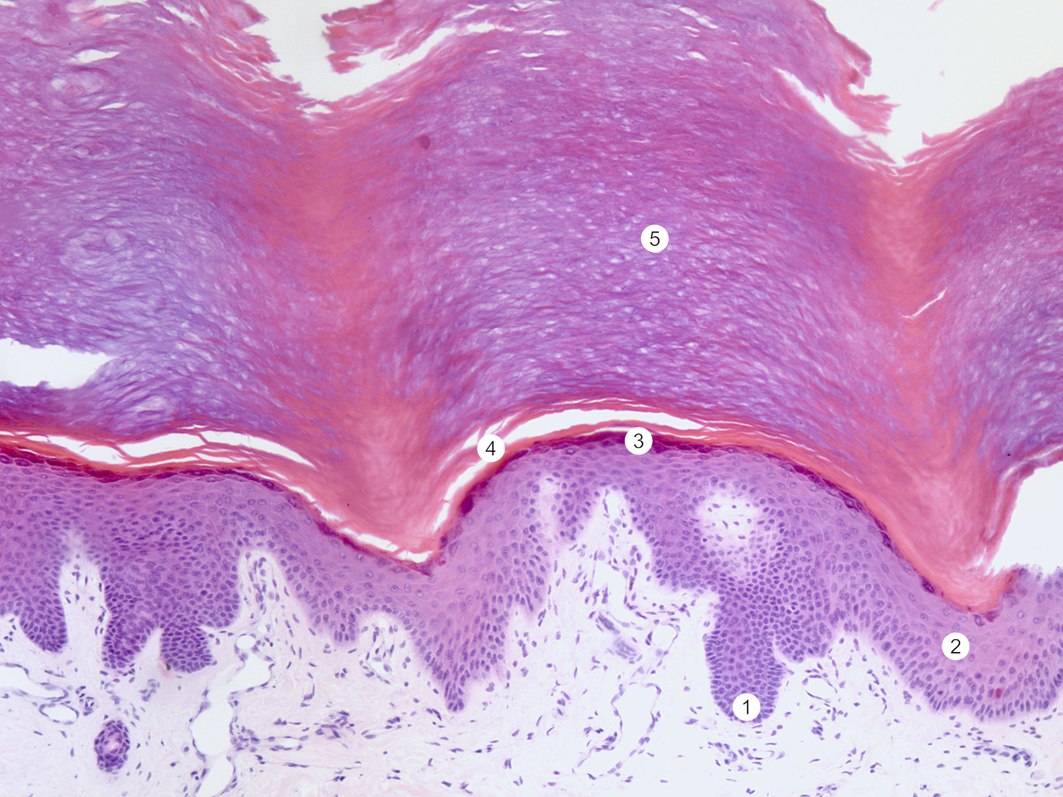

Препарат 1. Кожа с большим ороговением (кожа пальца). При малом увеличении видно, что в толстой коже имеется наружная эпителиальная часть — эпидермис. Под эпидермисом располагается соединительнотканная часть кожи — собственно кожа, или дерма. Эпидермис представлен многослойным плоским ороговевающим эпителием. Поверхность эпителия неровная, что обусловлено вдающимися в эпителий сосочками собственно кожи. В эпидермисе толстой кожи различают 5 слоев. Ростковый слой состоит из высоких кубических или низких призматических клеток базального слоя, связанных с базальной мембраной (1), и слоя шиповатых клеток, образованного 3–10 слоями (2). Клетки шиповатого слоя имеют ромбовидную форму и образуют короткие цитоплазматические отростки — шипики. Зернистый слой расположен над шиповатым и состоит из 2–3 слоев зернистых клеток, содержащих темноокрашенные гранулы кератогиалина (3). Блестящий слой (4) находится над зернистым, клетки содержат элеидин — продукт, образующийся из кератогиалина. Клетки не имеют ядер и органелл. Границы между клетками незаметны. На препарате слой выглядит как блестящая гомогенная полоска. Поверхностный толстый роговой слой (5) представлен уплощенными омертвевшими клетками, содержащими кератин, — роговыми чешуйками. Соединительнотканная часть кожи состоит из двух слоев. Непосредственно под эпидермисом, вдаваясь в него в виде высоких неправильной формы сосочков, располагается рыхлая волокнистая соединительная ткань — сосочковый слой. Слой содержит тонкие коллагеновые и эластические волокна, фибробласты, макрофаги, тучные клетки, капиллярные петли. Под сосочковым слоем расположен более толстый сетчатый слой, представленный плотной волокнистой неоформленной соединительной тканью. Для этого слоя характерно довольно плотное и беспорядочное переплетение толстых коллагеновых и тонких эластических волокон. Коллагеновые волокна образуют косо идущие пучки, проникающие в подкожно-жировую клетчатку. В сетчатом слое толстой кожи на границе с подкожно-жировой клетчаткой расположены секреторные отделы потовых желез. Гематоксилин, пикроиндигокармин. Препарат кафедры гистологии, цитологии и эмбриологии Казанского ГМУ.